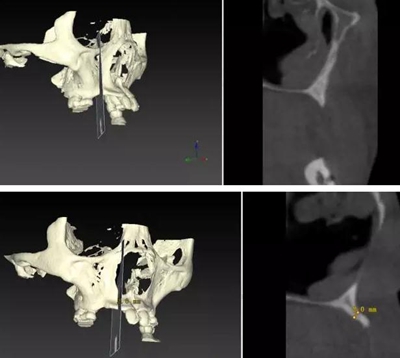

??茩z查:口內(nèi)僅剩16,11,21,26,雙側(cè)上下頜乳牙E滯留,其余恒牙缺失,上下頜骨發(fā)育不足,缺牙區(qū)牙槽嵴呈刃狀,上下頜弓比例協(xié)調(diào)。CBCT顯示:上頜前牙區(qū)牙槽嵴寬度約2-3mm,骨高度約10mm;上頜后牙區(qū)可用牙槽骨高度僅1-2mm,左右側(cè)上頜

竇內(nèi)粘膜有明顯增厚。下頜牙槽骨寬度及高度嚴(yán)重不足,僅存有基骨。

由于牙槽骨寬度嚴(yán)重不足,短種植體不適用于此類患者。因此,上述病例屬于難度極高的種植對象,讓很多種植醫(yī)生一籌莫展。

顴種植手術(shù)可以有效縮短該病例的治療周期,實(shí)現(xiàn)患者固定義齒修復(fù)的愿望。如果手術(shù)順利,患者有望在較短時間內(nèi)完成整個修復(fù)治療,恢復(fù)正常青年人的牙列狀態(tài)和外形,獲得自信,提高生活質(zhì)量。由于患者家境貧寒,種植手術(shù)材料費(fèi)用較高,目